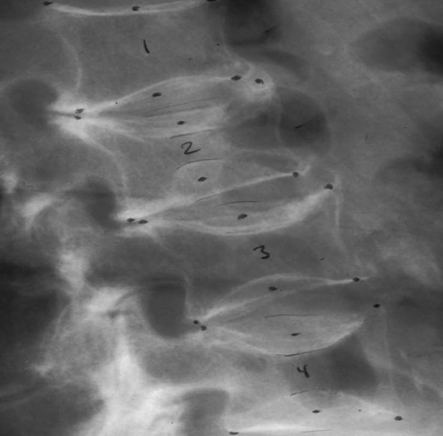

Types of fractures: to confirm the diagnosis, the radiograph must clearly identify the contours of the vertebral bodies to evaluate the decrease in any of the vertebral heights or break in the cortical edge and classify as wedge, biconcave or crushing Figure 5.

Figure 5 Placement of 6 points that delimit the vertebral borders and define anterior, middle and posterior height.

When morphometry is performed in lateral dorsolumbar radiology, it is known as MRX (radiographic vertebral morphometry), using the 6 points to determine anterior, middle and posterior heights as we see in Figure 5 and the “wedging indices” are used. “biconcavity index” and the “compression index”; leading to the definition of VF: as a percentage of decrease between 15 to 20% in their height or decrease in their indices as mentioned by J. Melton.4 Other authors such as Eastel, Mc Closkey and Minne have proposed other definitions, slightly modifying the previous ones.5–7